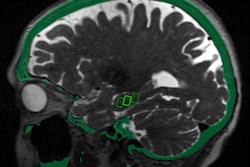

The U.S. Food and Drug Administration (FDA) has given clearance to researchers from the University of Maryland to proceed with a study that will investigate the use of MRI-guided focused ultrasound to open the blood-brain barrier.

The trial will be conducted with patients undergoing surgery for glioblastoma at the University of Maryland Medical Center (UMMC) in Baltimore. Sponsored by InSightec, which developed the technology that will be used in the study, it will involve injecting microscopic inert gas-filled bubbles into a patient's bloodstream and then moving them back and forth with targeted sound waves to stretch the blood vessel walls and create temporary openings.